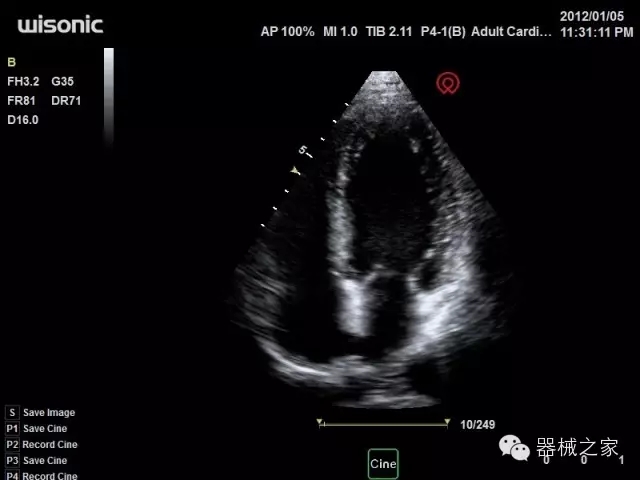

品牌:華聲醫(yī)療(WISONIC)

深圳華聲醫(yī)療技術(shù)有限公司成立于2012年,位于深圳南山西麗湖畔。是一家從事醫(yī)療設(shè)備研發(fā)、制造、營銷的新興高新技術(shù)企業(yè),目前提供生命信息支持、數(shù)字便攜彩超、移動醫(yī)療服務(wù)三個方面的業(yè)務(wù)解決方案。公司核心創(chuàng)始人均為醫(yī)療設(shè)備行業(yè)領(lǐng)軍人物,在醫(yī)療行業(yè)服務(wù)時間平均在10年以上,對行業(yè)和產(chǎn)品積累了深刻的認(rèn)識。公司在創(chuàng)立之初就有著長遠(yuǎn)的戰(zhàn)略目標(biāo)和規(guī)劃,致力于醫(yī)療設(shè)備行業(yè)的細(xì)分市場,貼近客戶所需,為大眾的健康提供更多關(guān)愛。

官方網(wǎng)站:www.wisonic.cn

經(jīng)典產(chǎn)品:四葉草

臨床圖片賞析

產(chǎn)品特點

·全球目前唯一一款配備主機雙探頭接口,整機重量(含電池)在5公斤以內(nèi)的便攜式彩超;

·一款互聯(lián)網(wǎng)彩超,只要有手機信號的地方就可以非常方便地實現(xiàn)遠(yuǎn)程會診和病案調(diào)取;

·鎂鋁合金外殼,堅固可靠耐用;

·獨有的HoloTM PW 實時3取樣門PW成像技術(shù),精確進(jìn)行血管診斷;

·一鍵優(yōu)化B、Color、PW,Auto Doppler自動識別血管位置、偏轉(zhuǎn)角度等,提高工作效率;

·30°超廣角精細(xì)偏轉(zhuǎn)成像技術(shù),更優(yōu)異的頻譜圖像;

·W+智能搜索引擎,快速尋找圖像;

·SSD、USB3.0保障開機快,導(dǎo)出圖像更快,減少等待時間;

·WIFI、網(wǎng)口、3G,多重聯(lián)網(wǎng)方式,全天候保障云端備份,不再擔(dān)心圖像丟失;

CFDA注冊證編號

·粵械注準(zhǔn)201522231208